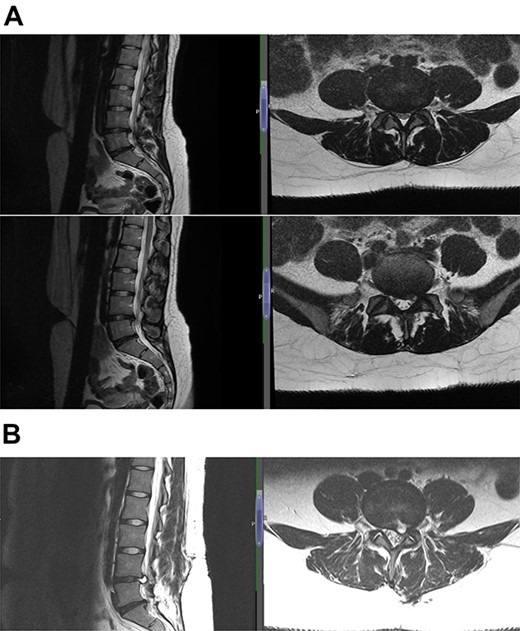

The diagnosis was reached keeping in mind the radiological and contrast scan was taken in follow-up period (Figs 1, 2a, b,3a, b and4a, b). On MRI, it was noted that the cyst was well-defined, smooth regular margins with T1 hypointense and T2 hyperintense and an evident communicating stalk with the disc while in post-gadolinium scan showed cyst wall enhancement. As discography is no longer required for reaching a diagnosis, it was not done in any of the patients.

(A) Case 2—initial MRI shows a slightly unusual abnormality associated with the L5-S1 compressing the left transiting S1 nerve root and is almost certainly a fragment of extruded/sequestered disc, and (B) case 2—updated MRI shows a significant decrease in the previously seen cystic lesion at L5-S1 level now measuring 4 mm (AP diameter, previously 11 mm).